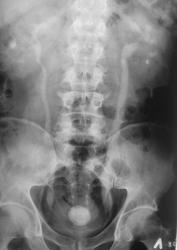

Фрагменты с увеличением.

Камень камнем, как объяснить этот мышинный хвостик внизу, а не обрубленная тень мочеточника? Приобретенный стеноз? выраженная стриктура? врожденная аномалия-мегауретер? или все таки стелещееся по стенке и устье образование? Хотя на пневмограммах стенка вполне приличная.

И, что писать в протоколе?

А то и писать-расширение левого мочеточника на протяжении диаметром до... юкставезикулярный отдел резко сужен, что не позволяет исключить... И посоветовать вашим "клиницистам" цистоскопию. Говоря о "блюдечке", а нам это тоже знакомо, тарелочка может разбиться-решение о ведении данного пациента вне зависимости от мнения рентгенолога остается за урологом, а если он будет рассказывать о том, как больной закровил и требовать решение-это не профессионал!  Лучевые методы исследования ВСЕГДА по приказам проводились после не лучевых инструментальных. Понятно, что рентгенологические исследования, как правило, безболезненные, а то что пациент при этом получил почти треть, а то и больше годовой дозы? Как заполнить ему радиационный паспорт и объяснить ему и "товарищам" через дорогу (там, пардон, у нас прокуратура, чтобы далеко не ходить), что уролог ручками и глазиком не поработал, а сразу шарахнули без защиты по полной программе. Извините за несколько грубый тон, но, поверьте, тоже достало!